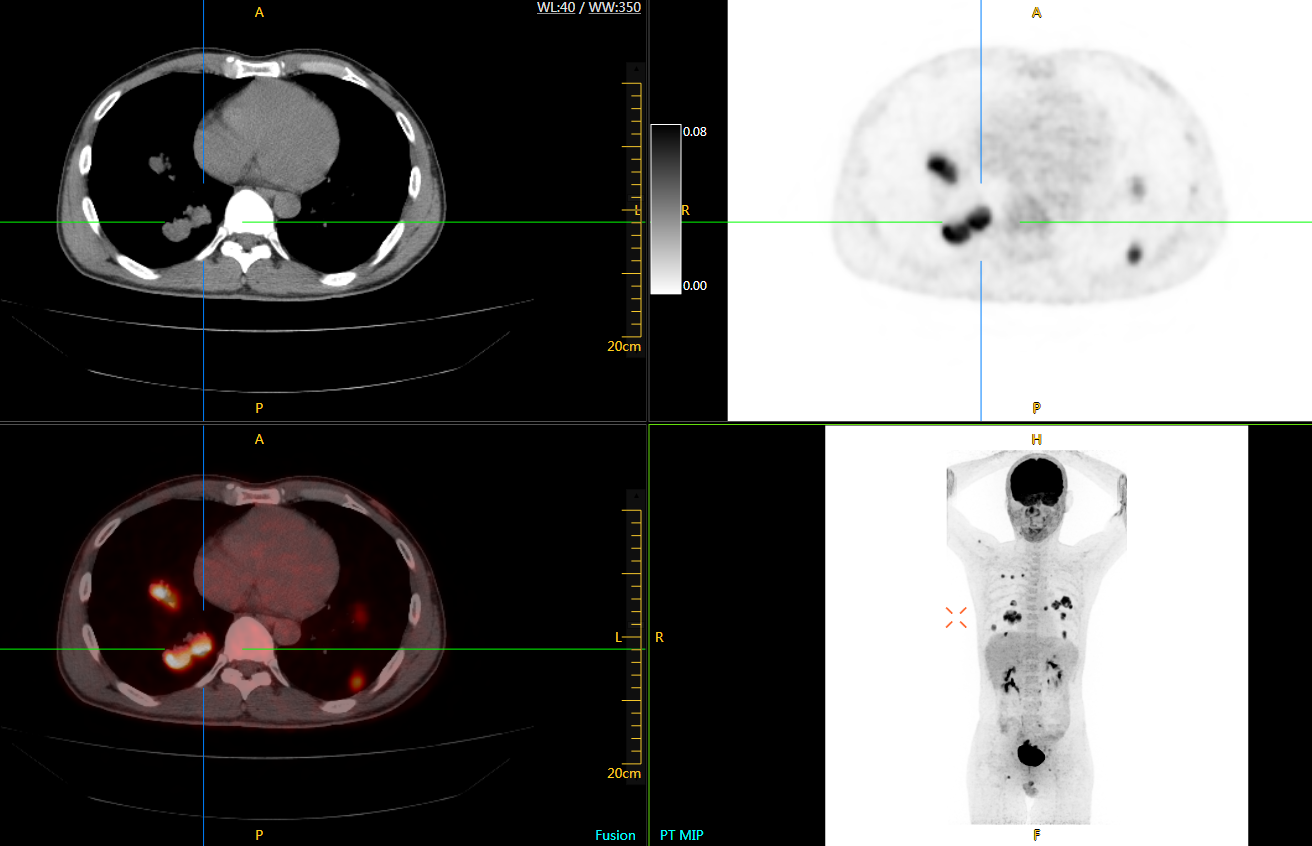

uExplorer探索者不再局限于傳統(tǒng)靜態(tài)代謝過程3D成像,而是在此基礎(chǔ)上新增一個(gè)維度——時(shí)間,從而實(shí)現(xiàn)4D全景成像。

注射總劑量為7.8mCi,14分鐘全身采集時(shí)間,在擁有超高靈敏度與超高分辨率的uEXPLORER上,即可得到展示顯示人體諸多精細(xì)結(jié)構(gòu)的高清三維圖像。

注射總劑量為7.8mCi,注射后1.6小時(shí),基于uEXPLORER探索者掃描1分鐘的圖像

注射總劑量為0.67 mCi FDG(低于常規(guī)劑量的十分之一),基于uEXPLORER探索者掃描15分鐘的圖像

注射總劑量為6.9mCi,注射后10小時(shí),基于uEXPLORER探索者掃描14分鐘的圖像